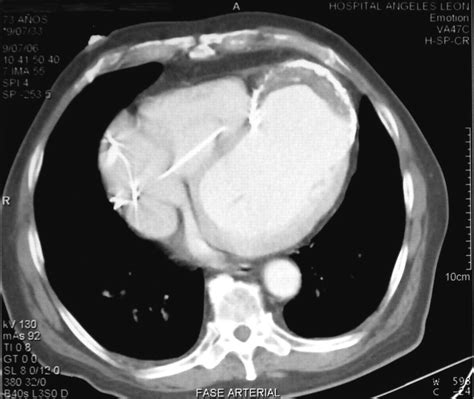

• Cardiac Magnetic Resonance Imaging (MRI): This provides detailed images of the heart and can help in diagnosing and assessing the severity of the aneurysm.

• left ventricular aneurysm ct